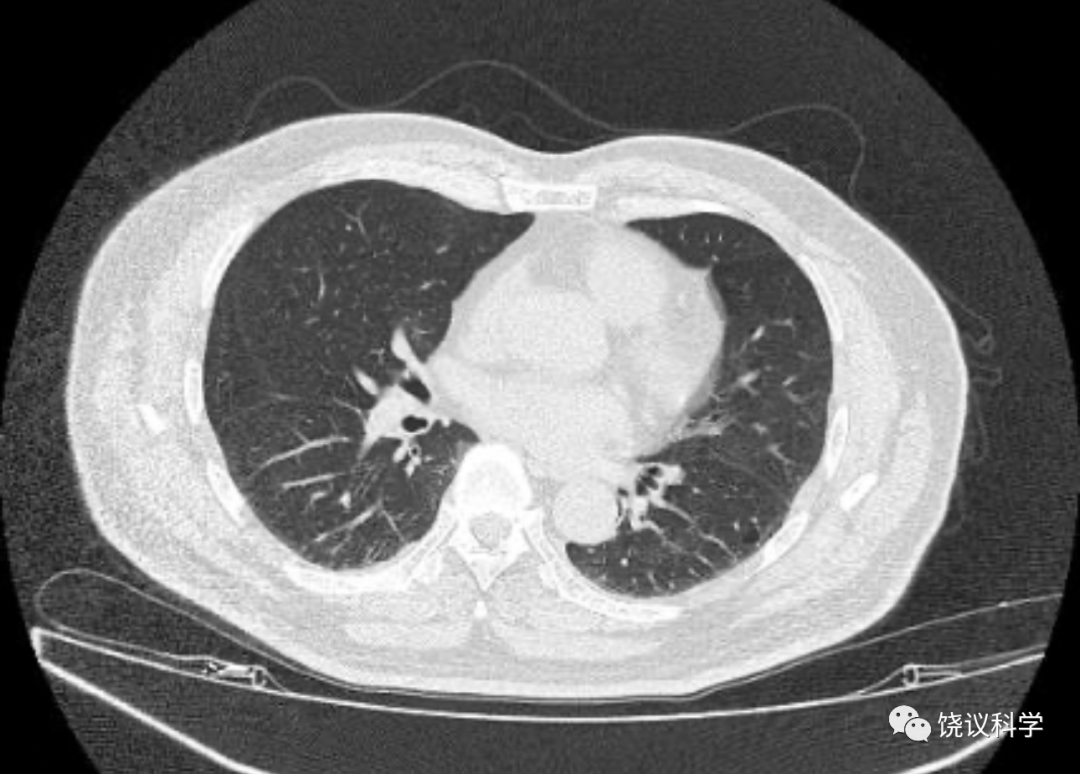

我們幾個有重有輕,最重的是高燒超過39度,輕的就是咽喉癢。沒人有呼吸困難、肺病變(這一類是以前致死的主要原因)。從這個意義估計我們問題都不大,應該能挺過去。